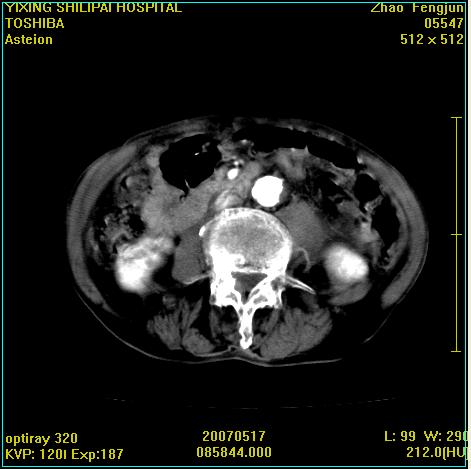

考虑:1、左侧腰大肌囊实性占位性病变(囊性神经根鞘瘤?);

2、右侧兰尾区囊性占位性病变(兰尾囊肿?囊腺癌?类癌?)

以下是引用xiaoniu在2007-5-26 10:45:00的发言:[br]腰大肌的病变应该没有问题,增强扫描还有轻度强化及细小血管影入内,应该排除脓肿,考虑占位性病变,腰大肌的占位多考虑:神经源性肿瘤。另外腹主动脉下端有真假腔的强化,考虑:主动脉夹层。[br][br][本贴已被 xiaoniu 于 2007-5-26 10:46:39 修改过]

以下是引用老爱克斯新网客在2007-5-26 18:26:00的发言:[br]1左下腹囊实性占位肿块,增强后不均匀强化,位于脊柱旁,椎体骨质无破坏软组织无肿胀,考虑神经源肿瘤神经鞘瘤可能大,2右下腹囊性占位性病变,增强后囊壁强化,考虑阑尾囊肿或囊腺瘤,